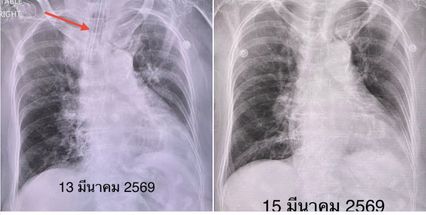

ทางด้าน นพ.มนูญ ลีเชวงวงศ์ แพทย์เชี่ยวชาญด้านระบบการหายใจและผู้ป่วยหนัก ใช้พื้นที่เฟซบุ๊กส่วนตัวแจ้งเตือนถึงไวรัสParainfluenza virus เช่นกัน โดยยกเคสผู้ป่วยหญิง อายุ 91 ปีมาโรงพยาบาลวันที่ 13 มี.ค.69 ด้วยอาการไอ เหนื่อย 1 วัน มาถึงห้องฉุกเฉิน เหนื่อยมากต้องใส่เครื่องช่วยหายใจ ย้ายขึ้นห้องไอซียู ที่บ้านมีคนป่วยเป็นหวัด 3 คน คือ ลูก หลาน และเหลน อายุ 2 ขวบ

ผู้ป่วยเป็นโรคหัวใจ ความดัน ไม่กินเหล้า ไม่สูบบุหรี่ เมื่อเดือน พ.ย.68 เคยติดเชื้อไวรัส RSV ตอนนั้นเกิดภาวะหายใจล้มเหลวเฉียบพลัน ต้องใส่เครื่องช่วยหายใจเหมือนกัน รอบนี้ผลตรวจร่างกาย มีไข้ อุณหภูมิ 38 องศาเซลเซียส ฟังปอดผิดปกติ เอกซเรย์ปอดไม่เห็นเงาผิดปกติ เจาะเลือด เม็ดเลือดขาวปกติ แยงจมูก ส่งตรวจสารพันธุกรรม พบเชื้อไวรัสParainfluenza virus type 4

แพทย์วินิจฉัยว่า ภาวะหายใจล้มเหลวเฉียบพลันจากติดเชื้อไวรัส Parainfluenza virus type 4 ให้การรักษาตามอาการ 2 วันต่อมาสามารถถอดเครื่องช่วยหายใจได้เอกซเรย์ปอดปกติดี ย้ายออกจากห้องไอซียูได้